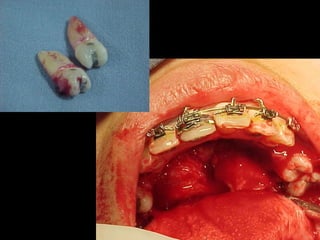

La paciente fue manejada iatrogénicamente por 5 años

Utilizando diferentes implementos ortodóncicos

La regla es clara: Laterognatias de más de 2º son quirúrgicas

La paciente fuemanejada iatrogénicamente por 5 años Utilizando diferentes implementos ortodóncicos La regla es clara: Laterognatias de más de 2º son quirúrgicas